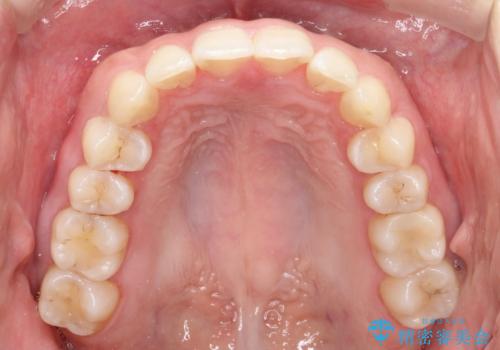

【インビザライン】翼状捻転+出っ歯を治したい

- 前歯の捻れと口元の突出を主訴に来院されました。

インビザラインを用いて上顎の遠心移動を行い、前歯を下げながら凸凹を綺麗に治すことができました。

歯を抜かない矯正治療を行う場合、口元は極端には変わりません。

今回は奥歯の遠心移動を行い、できる限り前歯を下げられるように治療を行いました。